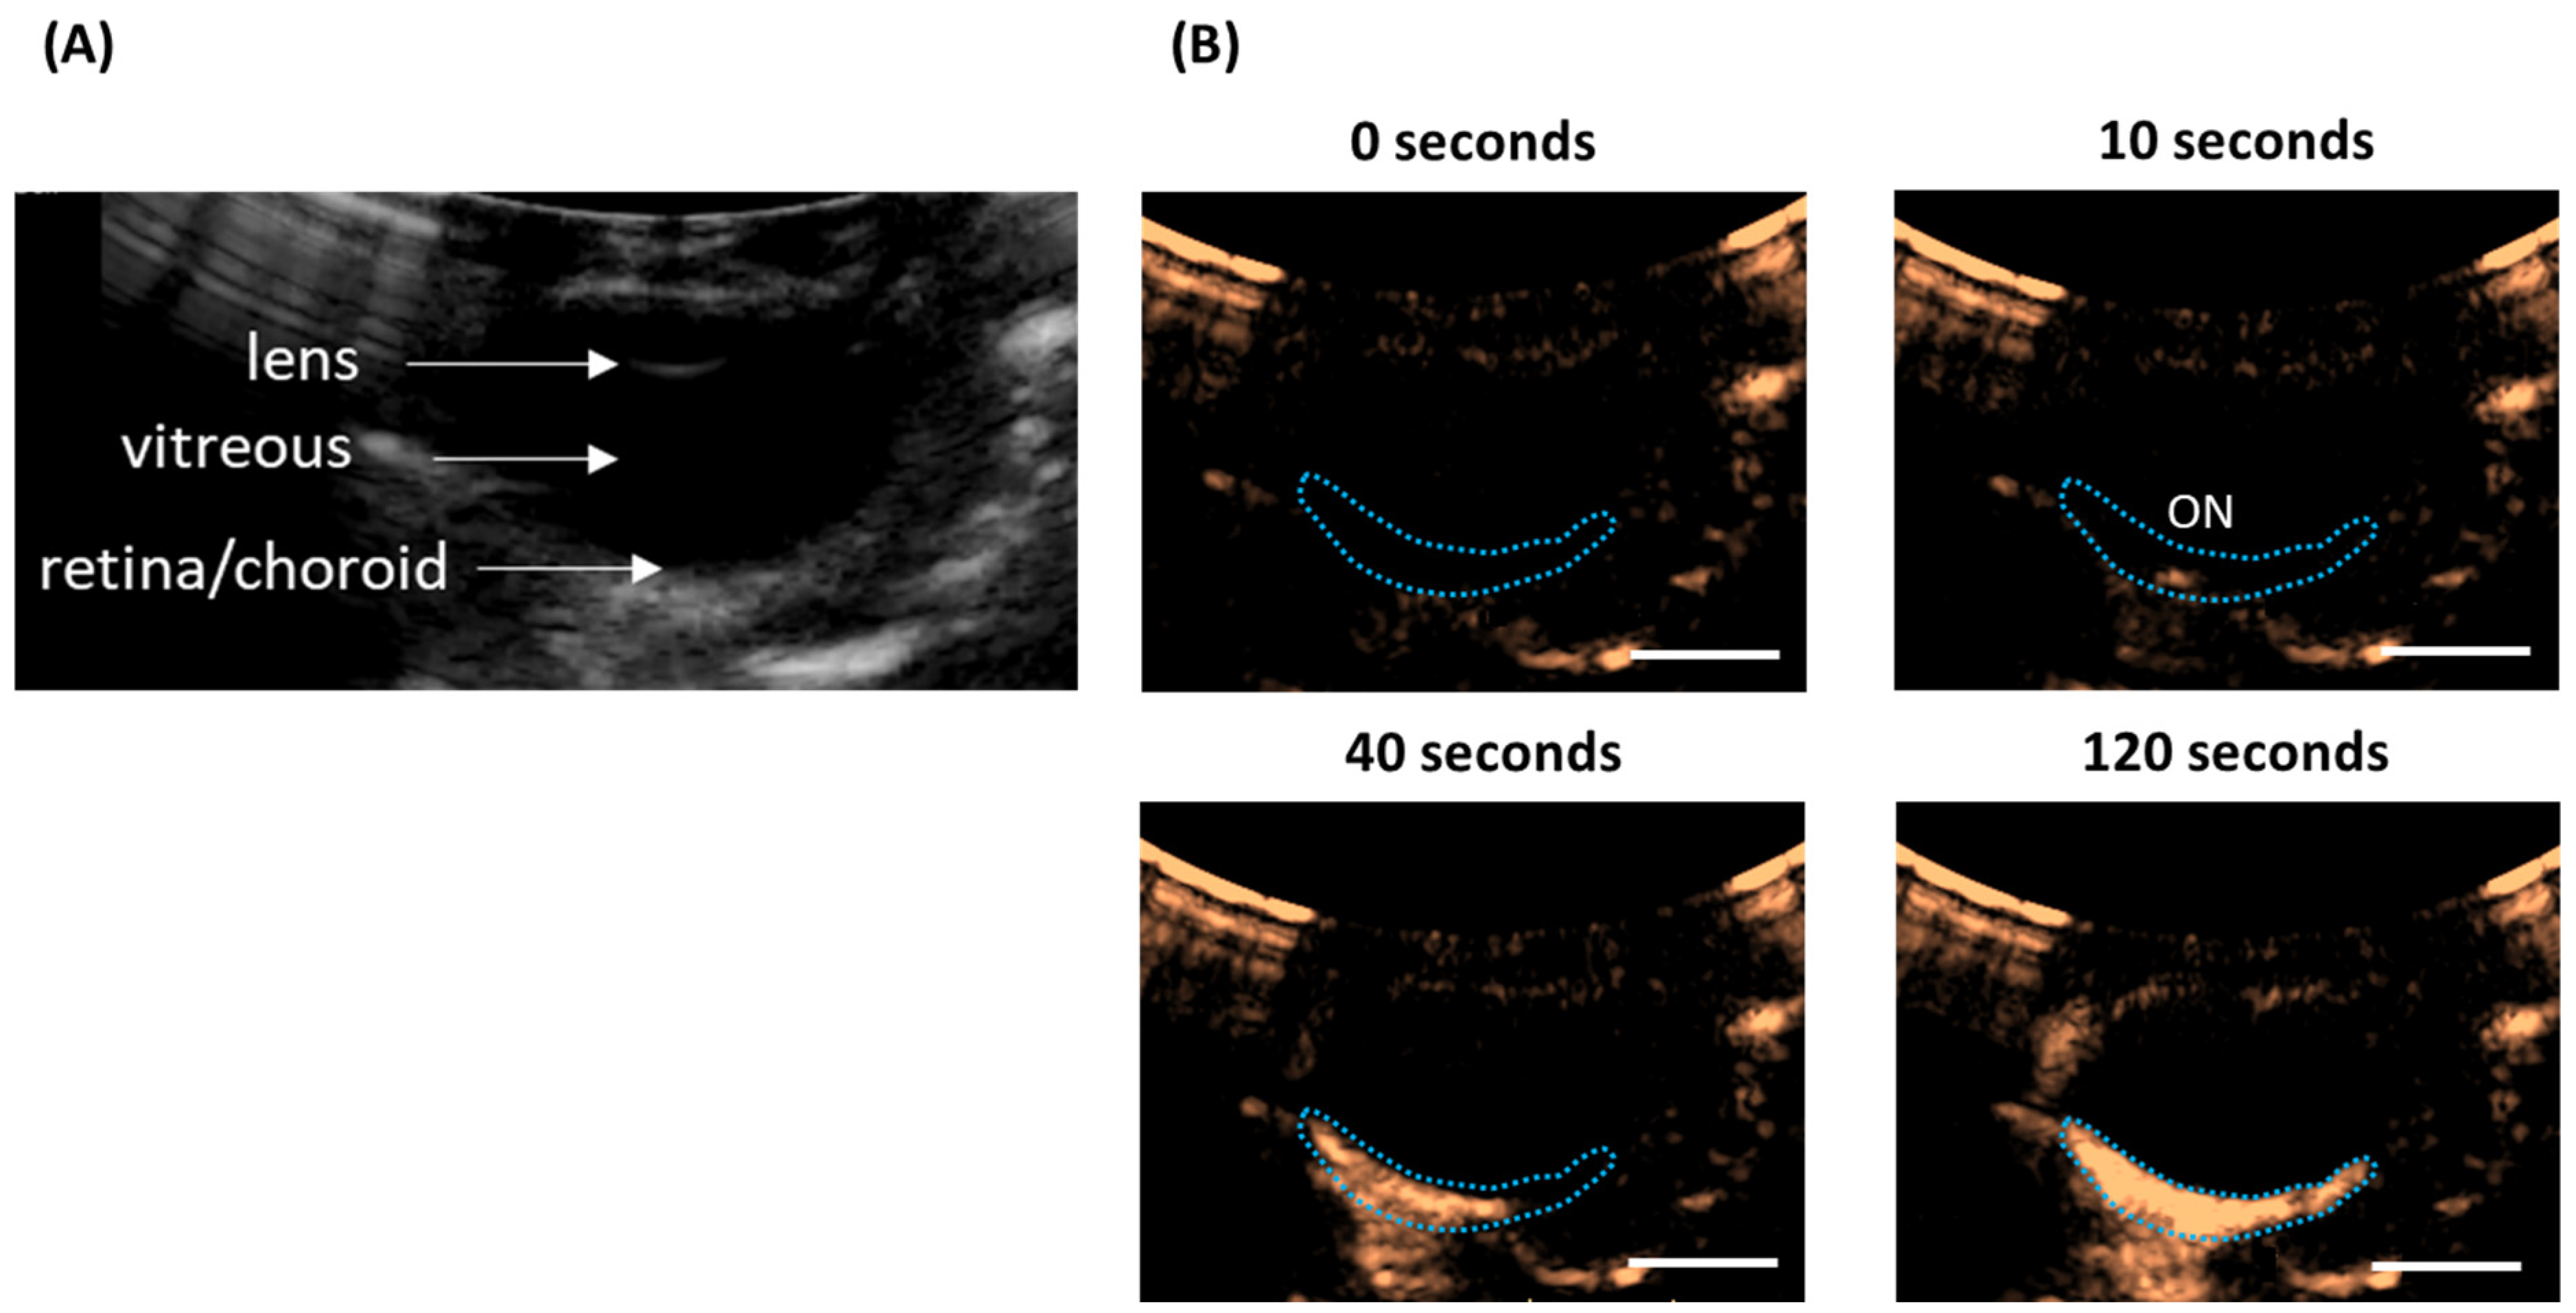

5.1. Microbubble Circulation in the Posterior Segment of the Eye